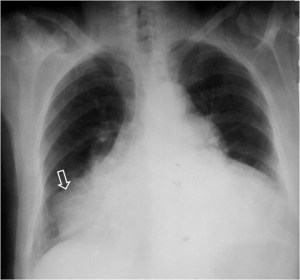

SIGNO DE LA ALTERACIÓN DEL CONTORNO AÓRTICO

La irregularidad, abombamiento o borramiento del arco aórtico en la radiografía de tórax en bipedestación o en decúbito supino, en un paciente con traumatismo torácico, obliga a descartar rotura aórtica como causa de dicha alteración. La flecha muestra el contorno aórtico anómalo. Además, hay un aumento de densidad en el hemitórax izquierdo correspondiente a derrame pleural –hemotórax en este caso-, que refuerza la sospecha de rotura aórtica.